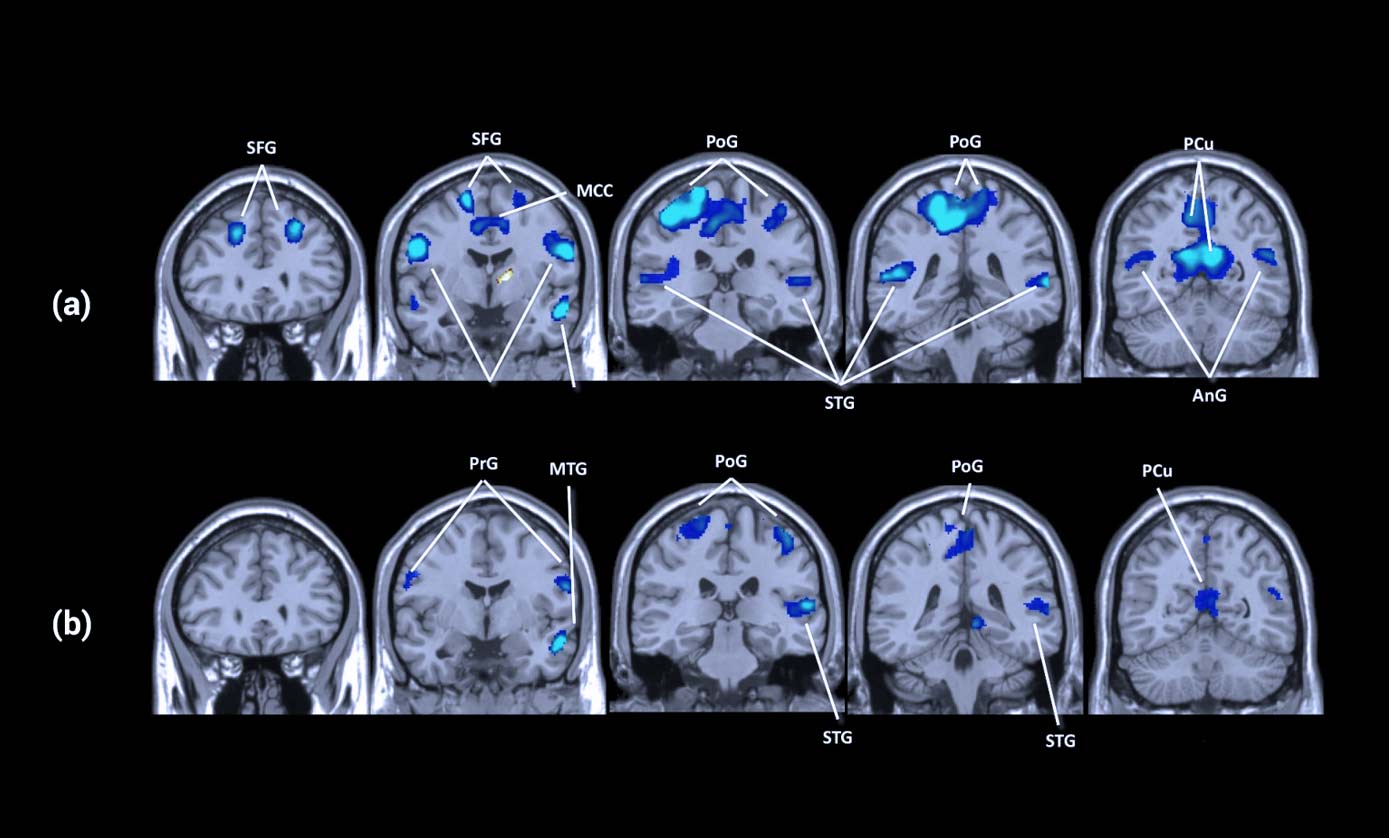

In a recent study [2], 36 people with chronic tinnitus lasting 3 months or longer were assessed with either active or placebo tVNS treatment. Active treatment used an electrode connected to part of the outer ear which innervates the vagus nerve whereas placebo treatment used a part of the outer ear with no vagal innervation. Brain scans were obtained to provide visual interpretations of the tVNS effects.

These scans revealed that tVNS stimulation activates the locus coeruleus (LC) and nucleus of the solitary tract (NST) in the brainstem which then projects to these other key brain regions. The treatment was found to deactivate the auditory system including the superior temporal gyrus, Heschl's gyrus, planum polare and planum temporale. These observations suggest that tVNS can modulate the dysfunctional auditory cortex and induce selective suppression of tinnitus-related brain regions.

In addition, tVNS also induced the deactivation of the limbic system which was implicated in the generation of tinnitus. It was thought that abnormally strengthened signal transductions between the auditory, limbic and attention systems were the main mechanisms behind the worsening of tinnitus. These overactive systems intensified the neural transmission of tinnitus signals within the brain. This new research suggests two main neurological mechanisms contributing to the experience of this phantom sound, auditory-cortex-related tinnitus associated with little or no hearing loss, and parahippocampus-related tinnitus associated with more severe hearing loss [18].